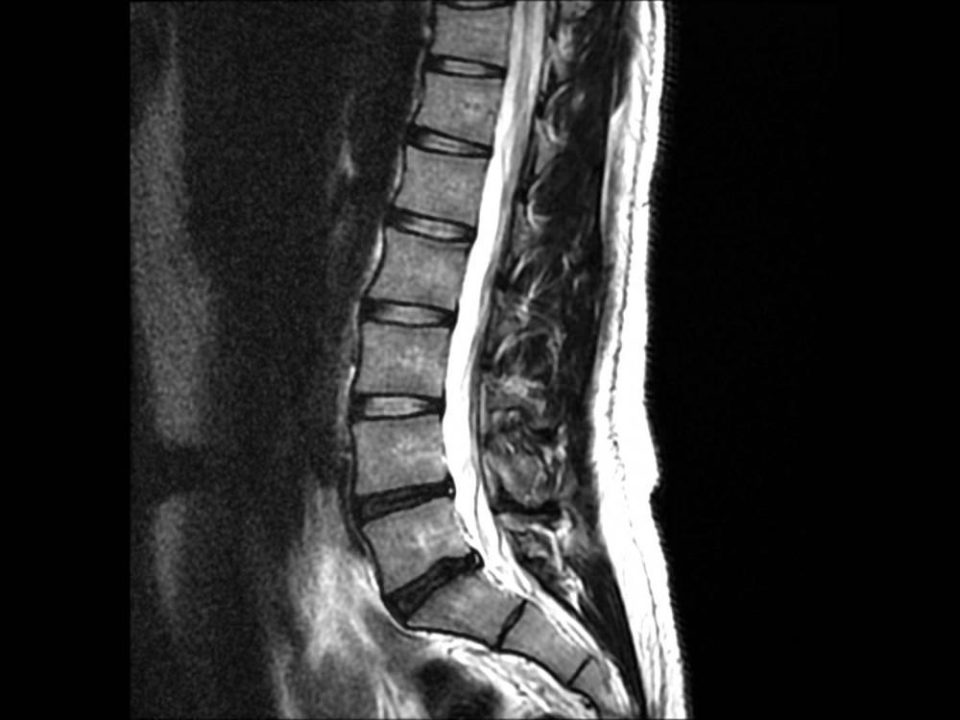

The Ontario government recently announced that they will begin consultations on a proposal to allow chiropractors to order advanced imaging like MRI, CT scans and diagnostic […]

New Study Finds Chiropractic Helps Reduce Need for Low Back Reoperation

A study published earlier this year suggests that patients who require back surgery are less likely to need further surgery if they have chiropractic treatment. Researchers […]